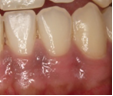

健康な歯肉は綺麗なピンク色をしています☆

みなさんの歯肉はどうですか??

せっかく治療をしたりホワイトニングをして綺麗な歯になったのに、歯肉が黒ずんでいるのは

もったいないですよね>_<

黒ずんだ歯肉をきれいなピンクの歯肉に戻す方法で歯肉ピーリングという処置があります☆

歯肉に薬品を塗布し、2~3日でメラニン色素を含んだ歯肉の表層が脱落し、

1~2週間で新しい表層が再生され、きれいな歯肉に生まれ変わります。

| 術前 | 塗布直後 | 塗布30分後 | 術後 |